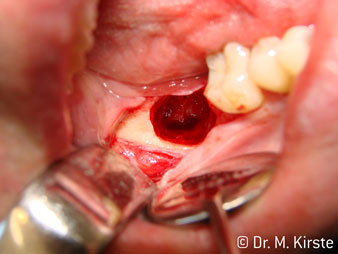

45° ъгъл на наконечника е специално избран поради неговата широка гама от предимства. Колеги, които работят хирургия, и за които този наконечник е главно създаден, скоро ще оценят възможността за ефективна работа в силно ограничени пространства. При екстрахиране на мъдреци, в частност (фиг. 2), няма нужда от голямо разширяване на меката тъкан в областта на бузата (фиг. 3). Дизайнът на главата на наконечника, в съчетание с лекото завъртане на главата по време на препарация, позволява бърза и безопасна работа в ретромоларната област.

Специалният дизайн на лагерите в главата на наконечника гарантира безшумен ход на борера; това прави впечатляващо атравматичен разрез при отделянето на зъба и корена (фиг. 4-9).